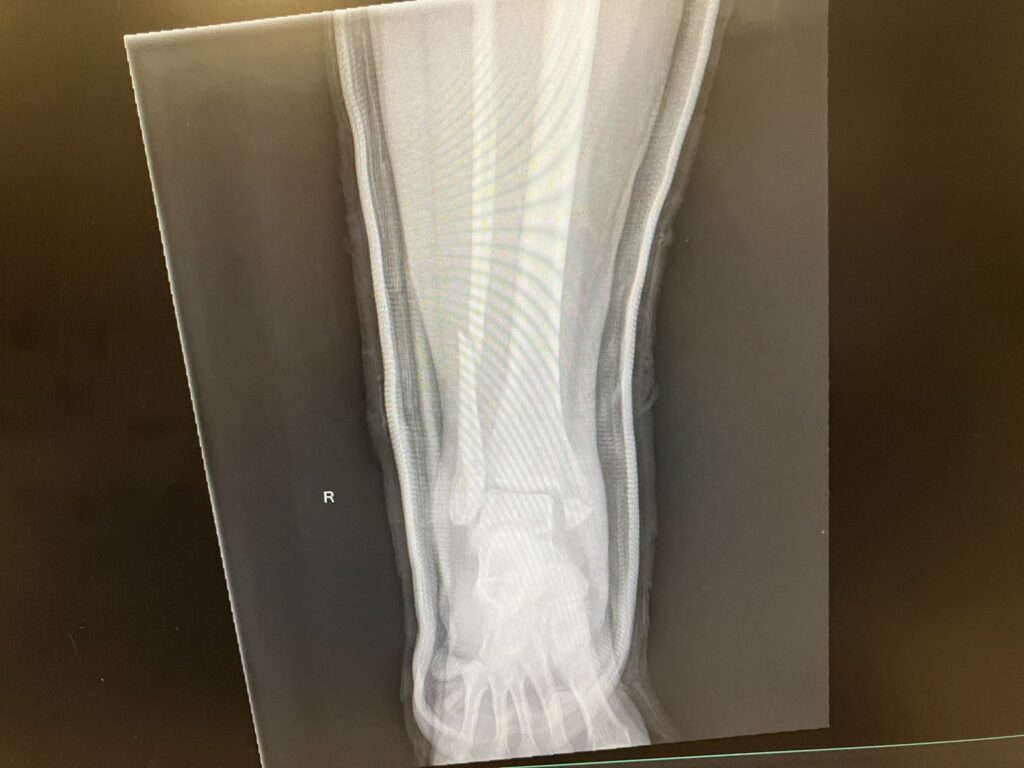

Sorry to report that I spent a few days in the hospital. I was carrying foster puppy KALI outside to potty Sunday afternoon, and I slipped on some ice and fell. Broke my ankle, dislocated my ankle, and broke both bones in my shin. Sunday night they sedated me to yank everything back into alignment. All hail good meds. Apparently, I narrated my hallucinations. I had surgery Monday morning, and they pinned, screwed, and plated everything back together. Sounds like 8-10 weeks of NON-weight-bearing life for me. Gah! They gave me a nerve block before surgery, but that’s starting to wear off now now that I’m home, etc.

Before and after surgery x-rays. They realigned things Sunday evening in the ER. Gave the team a little scare when I stopped breathing for a bit, but I guess they hollered and shook me, and I started breathing again. Instead of your regular old orthopedic surgeon, they have a team of trauma / ortho surgeons who specialize in piecing people back together. I’m so grateful to receive access to their skill and expertise.